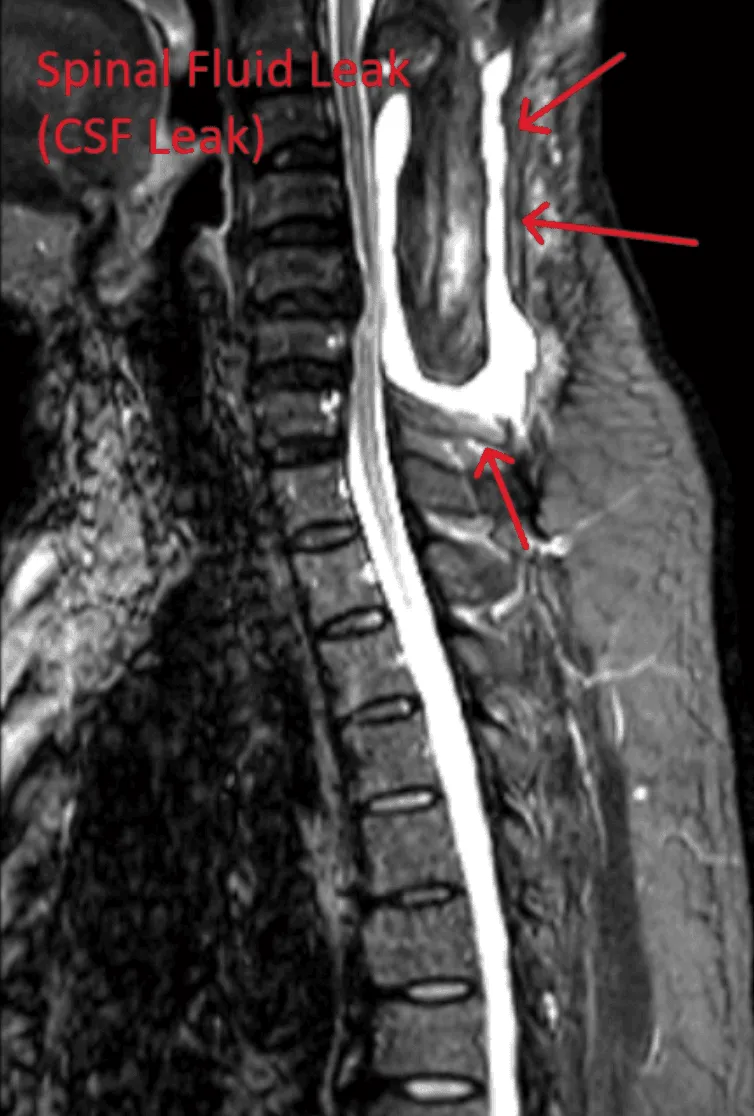

MRI showing cerebrospinal fluid leak with arrows indicating affected areas.

Spinal Fluid Leak

Dural tears leading to cerebrospinal fluid leaks, requiring additional repair surgery.